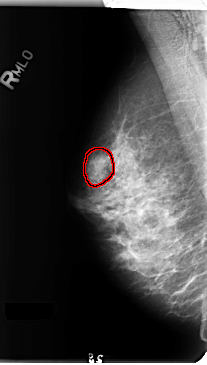

B_3156_1.RIGHT_MLO

RIGHT_MLO LINES 4736 PIXELS_PER_LINE 2680 BITS_PER_PIXEL 12 RESOLUTION 50 OVERLAY

FILE: B_3156_1.RIGHT_MLO.OVERLAY

TOTAL_ABNORMALITIES 1

ABNORMALITY 1

LESION_TYPE MASS SHAPE OVAL MARGINS CIRCUMSCRIBED-OBSCURED-ILL_DEFINED

ASSESSMENT 4

SUBTLETY 3

PATHOLOGY BENIGN

TOTAL_OUTLINES 1

BOUNDARY